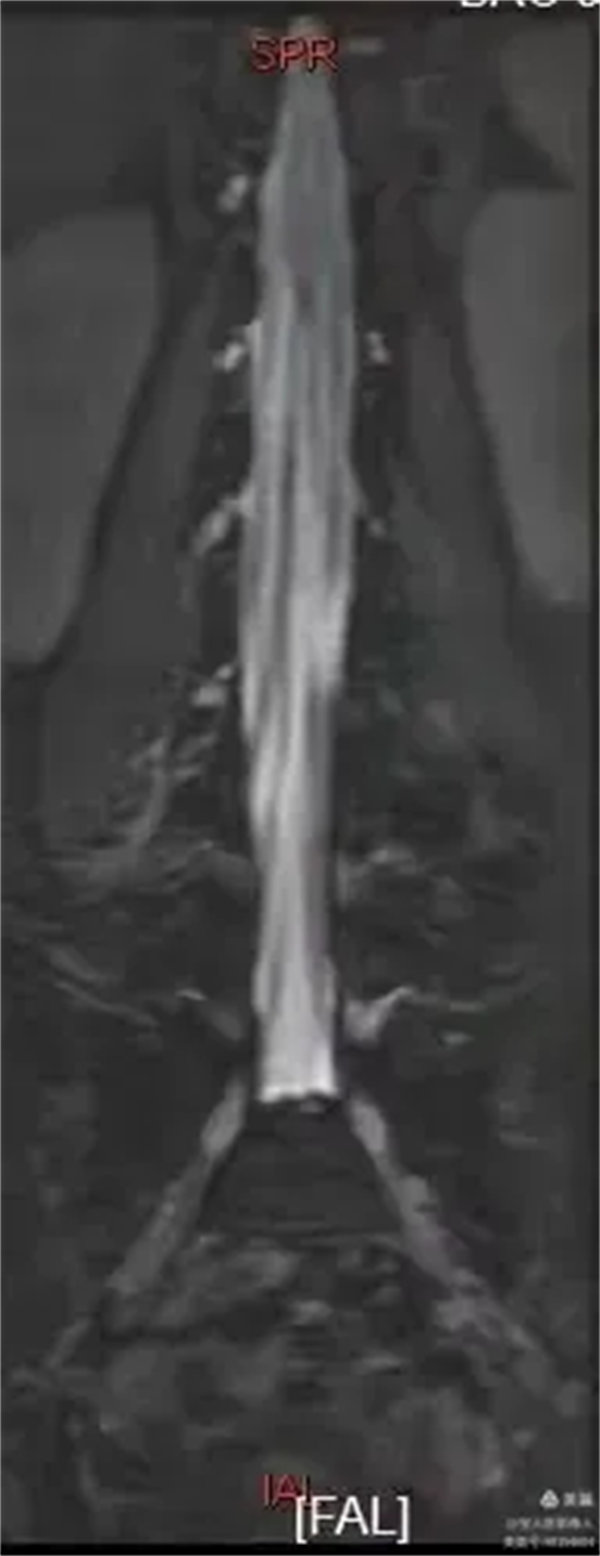

容積成像和最大密度,顯示腰段腦脊液正面圖。

最大密度正面圖,顯示腰段腦脊液(高信號),其內的馬尾神經以及腰神經(線狀稍低信號)。